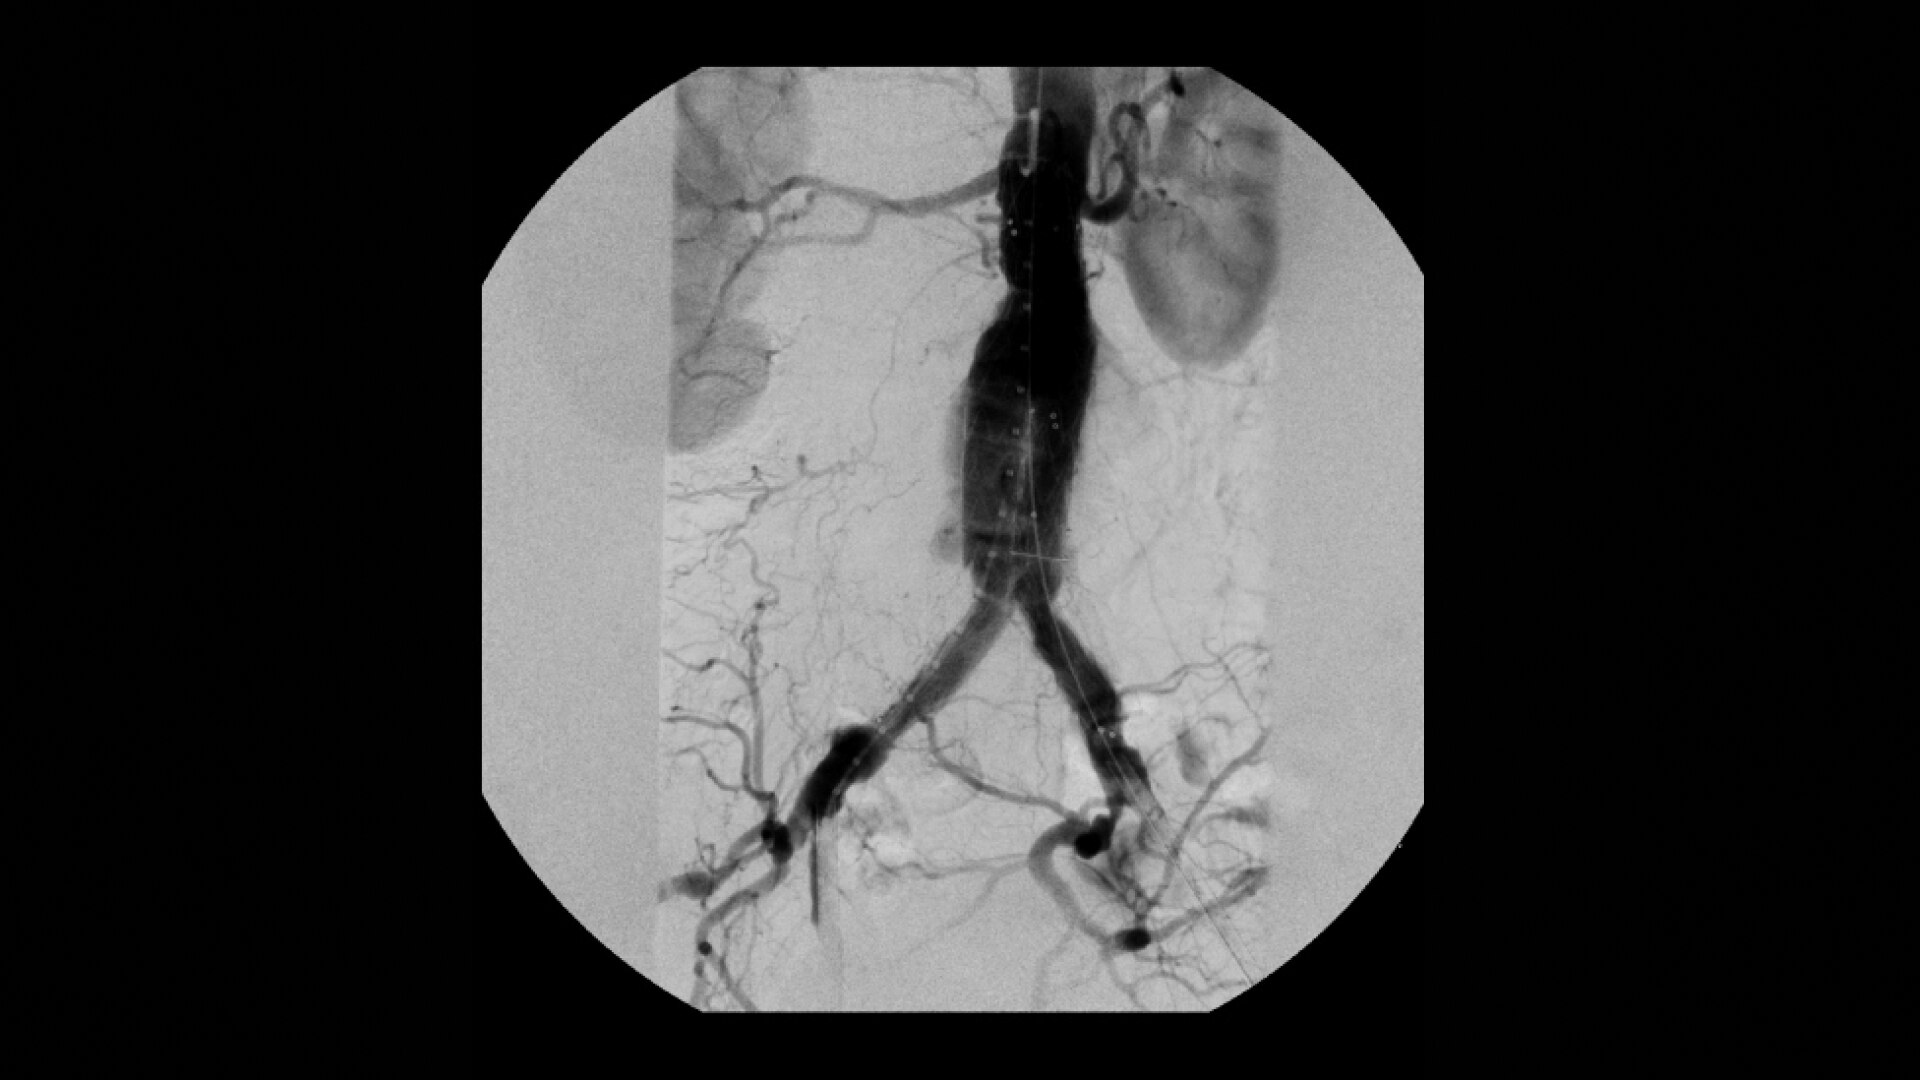

Clearly see 0.014” guidewires in chest and abdomen region or 0.008” guidewires in peripheral vascular with the OEC Elite CFD with a flat detector, image processing advancements and 4K viewing display.

Experience fixed room-like images with eNR (enhanced Noise Reduction), an advanced software algorithm that automatically reduces image noise by 30% for an equivalent appearance of 30 kW power.